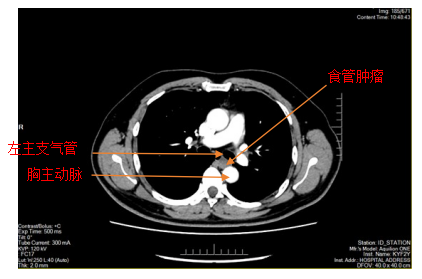

胸部增强CT

患者李某因胸骨后异物感20余天入院,在外院进行胃镜检查提示食管距门齿约26cm处见黏膜下肿瘤,在财神捕鱼 超声胃镜提示该肿瘤呈低回声,局限于黏膜下层,固有肌层完整;胸部CT提示该肿瘤直径>2cm,位于食管中下段,增强扫描轻度强化,前与左主支气管相邻,后紧贴胸主动脉,手术过程中稍有不慎就可能发生大出血,危及患者生命,手术难度和风险可想而知。